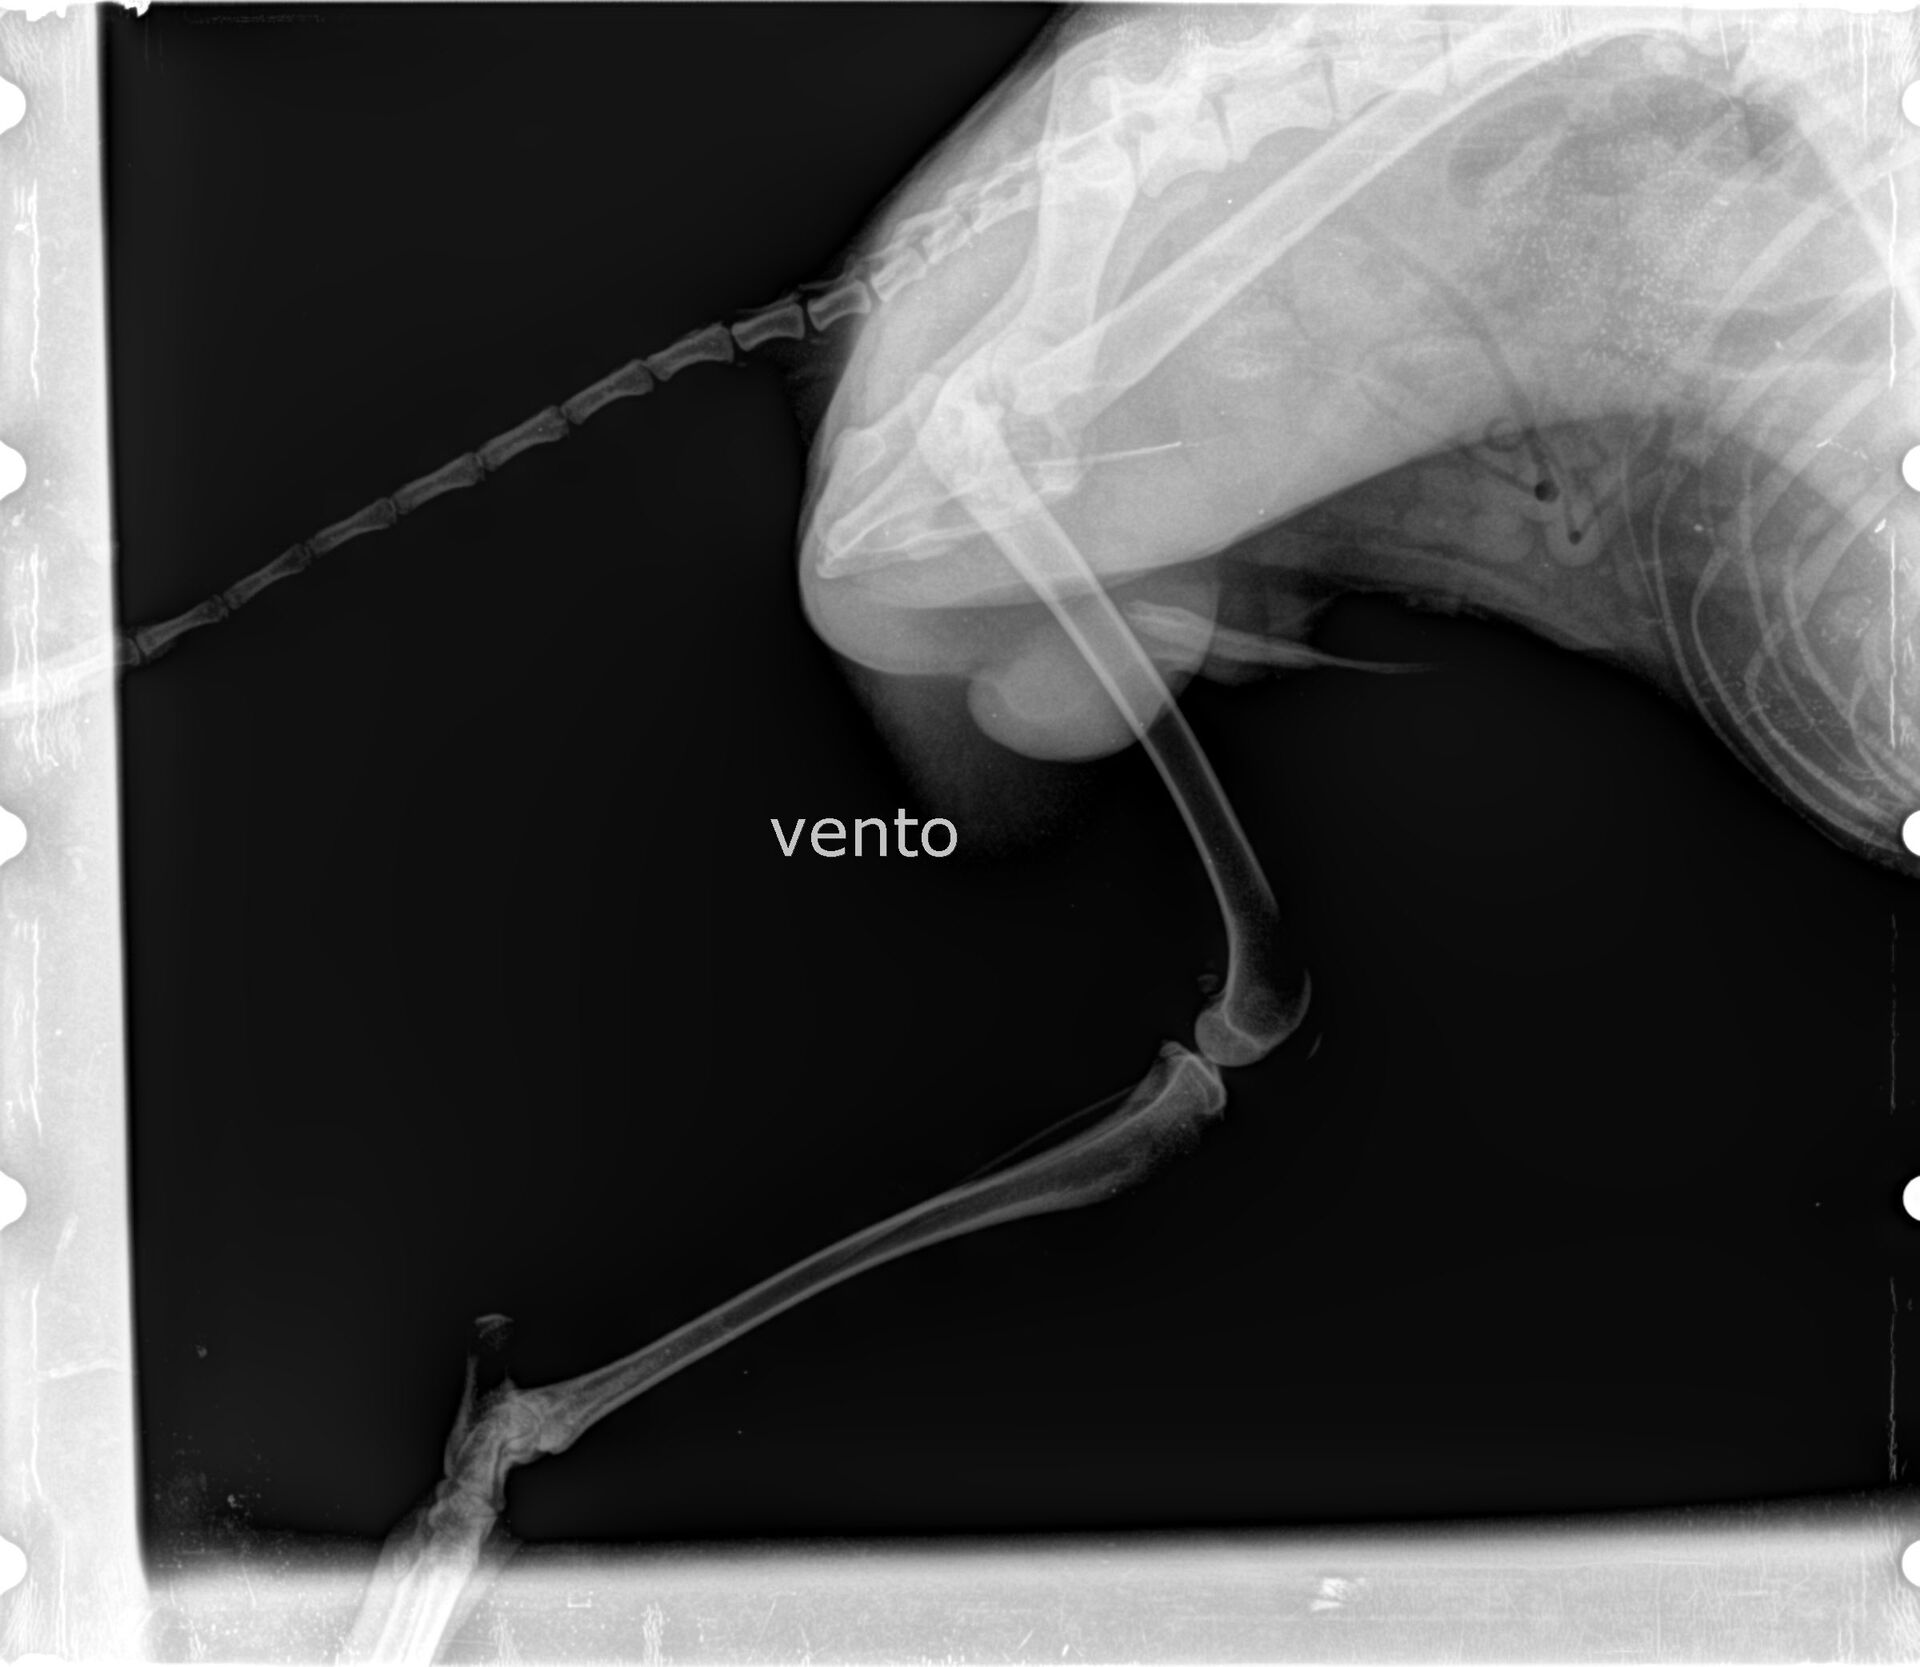

Vento wurde heute kastriert. Da uns aufgefallen war, dass er hinten links hinkt und schont, wurde während der Narkose geröntgt. Diagnose: Er hat eine alte Verletzung am Oberschenkelkopf, die degeneriert ist und zu Lahmheit, Gelenkschmerzen und Verlust von Muskelmasse führt. Exzisionsarthroplastik wird empfohlen.